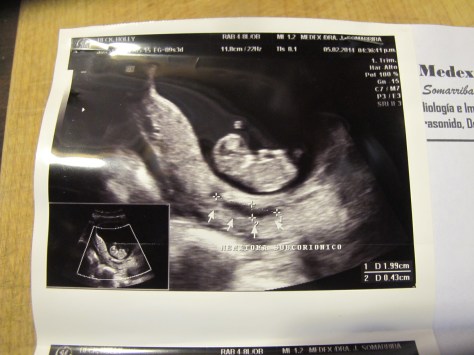

Then at 9.5 weeks I had some spotting. It was light in volume and dark in color, which everything I could find on the internet told me was probably ok, but I was nervous. When there was a bit more spotting the next day, I freaked out and we went to the Dr. immediately. I then had my second ultrasound which confirmed that everything was ok. I actually got to hear the heartbeat for the first time! The Dr. told me the bleeding was caused by a subcorionic hematoma – a not uncommon and not usually serious separation of the uterus and chorionic membrane. It can be a problem if it’s large, but luckily mine was small. I’d had a cold a few days before and a really bad cough that had me hacking all night with some fierce core-shuddering coughing spasms. That was most likely the cause. I was advised to take it super easy – bed rest for three days – and then the absolute minimum amount of activity for two weeks to let it heal. He also advised another ultrasound in 2 weeks to make sure it was gone.

So, at 12 weeks, I got another ultrasound. My third. My friend Nikki who is also pregnant here had recommended a new Dr. who is young, was educated in London, and seemed better to her than the Dr. we’d both been seeing previously. I made the switch as well and he informed me that he’s the only Dr. certified to perform the 12 week chromosomal abnormality tests that identify risks for defects such as Down Syndrome. Nikki had just had this test done and raved to me about how awesome it was to see all the physical structures and the relief of hearing she was low risk. When the Dr. asked if I was interested, I said “yes, please”.

If I had already read the section on ultrasounds in Margulis’ book, I would not have opted to have the test done. The test ended up taking about 30 min of pure ultrasound time (in an hour long appointment), and while it was really fun to see all the fingers and toes, and be told that I was also low risk and all the parts looked normal and healthy, after reading more about ultrasounds I don’t think it was worth it. But I was also happy to see that my hematoma was gone.